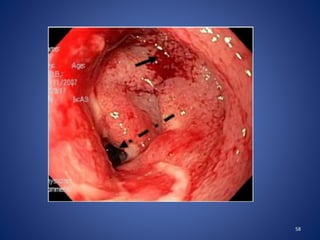

56

Nodules

Variable sizes (2 to 6mm)

Non friable

Most common in caecum especially near IC valve.

Tubercular ulcers

Large (10 to 20mm) or small (3 to 5mm)

Located between the nodules

Single or multiple

Transversely oriented / circumferential contrast to Crohns

Healing of these ‘girdle ulcers’ strictures

Deformed and edematous ileocaecal valve

57

58